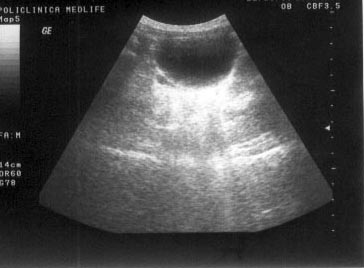

SEMIOLOGIE ECOGRAFICA

SEMIOLOGIE ECOGRAFICA Ecografia foloseste notiuni semiologice bine definite care incearca sa explice modificarile produse de traversarea ultrasunetelor prin tesuturi cu densitati diferite. Informatia ecograCiteste tot ... 2060 cuvinte